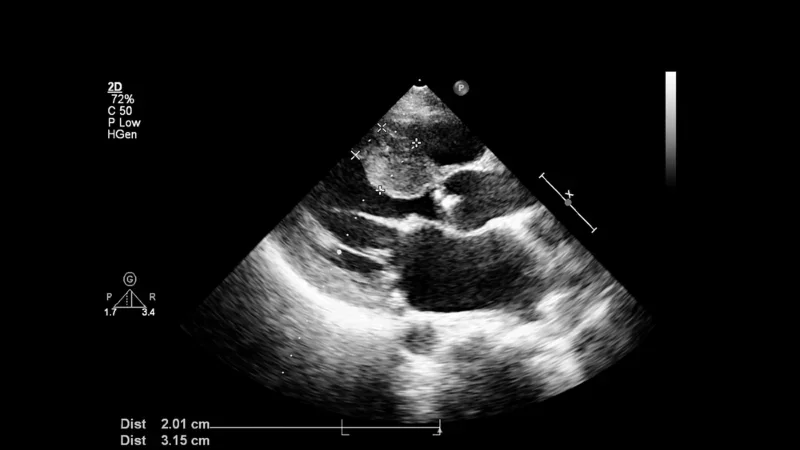

超音波検査は、排卵後12〜14日で妊娠を確認できるため、牝馬の妊娠を診断するために現代の獣医診療で使用される最も一般的な手法です。お腹の中の子馬が適切に発育しているかどうか、そしてそれが健康であるかどうかを判断するために、超音波は必要不可欠でした。

獣医は超音波で2つの奇妙なことに気づき、そのうちの1つはフェリシアの腹にある医療用チップでした。獣医はそれを見たとき、警察に電話しなければならないことを悟りました。それはベンを助けた専門家によって違法に作られたものであり、フェリシアの状態につながった可能性もあり、警察はそのチップを探していました。

獣医が超音波で気づいた2番目のことは、この仔馬はまれなタイプであり、多額のお金の価値がある可能性があるということでした。手術が行われ、フェリシアが仔馬を出産したとき、獣医はその目を信じることができませんでした。それは、多くの動物を見て来た獣医でさえこれまで見たことがなかったものでした…